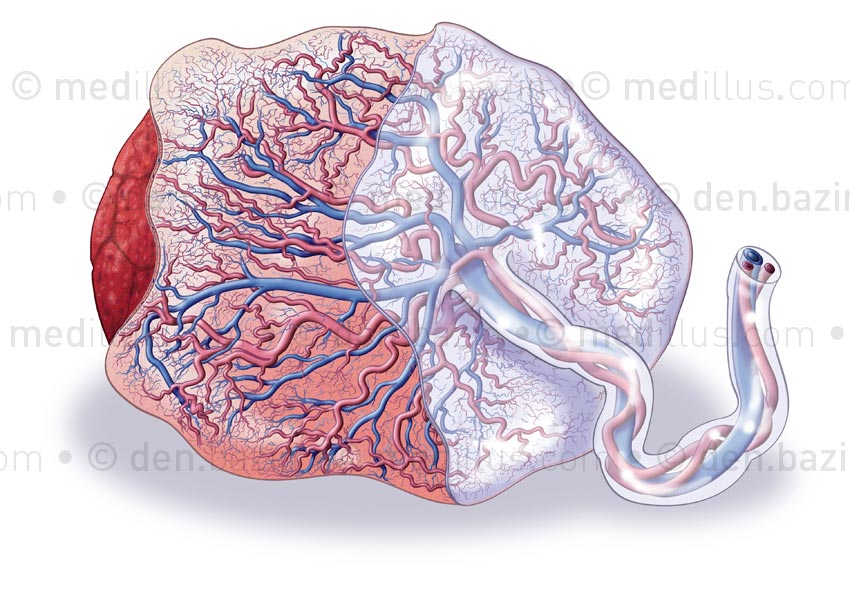

Placenta